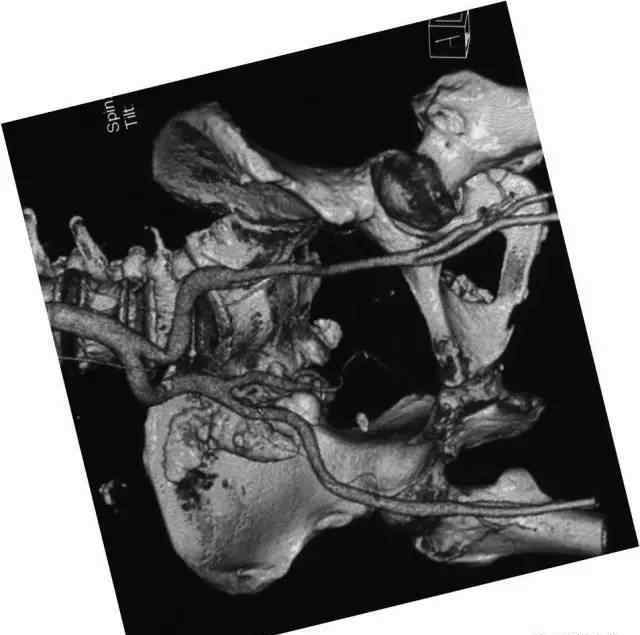

临床病史,女,60岁。主要原因是骶尾部疼痛20多年,20多年前骶尾部疼痛无诱因,为针刺样疼痛,辐射至右下肢,局部诊断为“坐骨神经痛”。体检:各椎体棘突、椎旁、双侧骶髂关节未见明显压痛和扣痛。皮肤无静脉扩张,皮肤温度不高。

图像:

手术记录:术中发现肿瘤累及髂骨、骶髂关节和部分骶骨,大小约12x10x10cm,肿瘤内含有钙质组织。

病理结果:(右侧骶髂关节)结核伴钙化